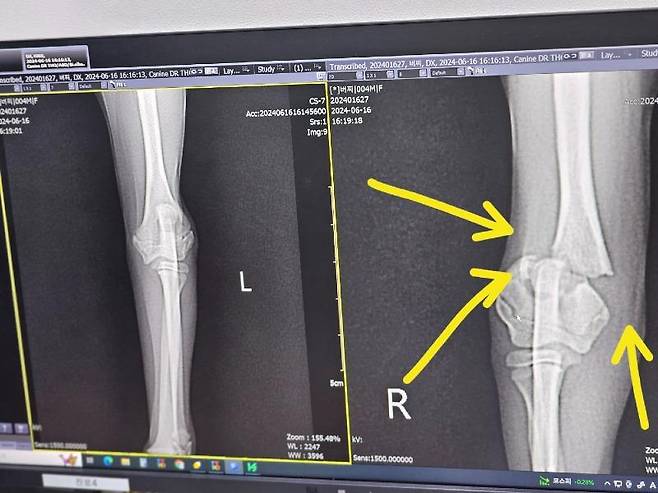

병원을 가 보니 다리 관절이 분쇄골절, 수술비는 무려 500만원 이상 나오게 되었습니다. 그리고 관절 근처이다 보니 난해한 수술을 마치더라도 장애 및 후유증이 동반할 수 있다고 합니다.